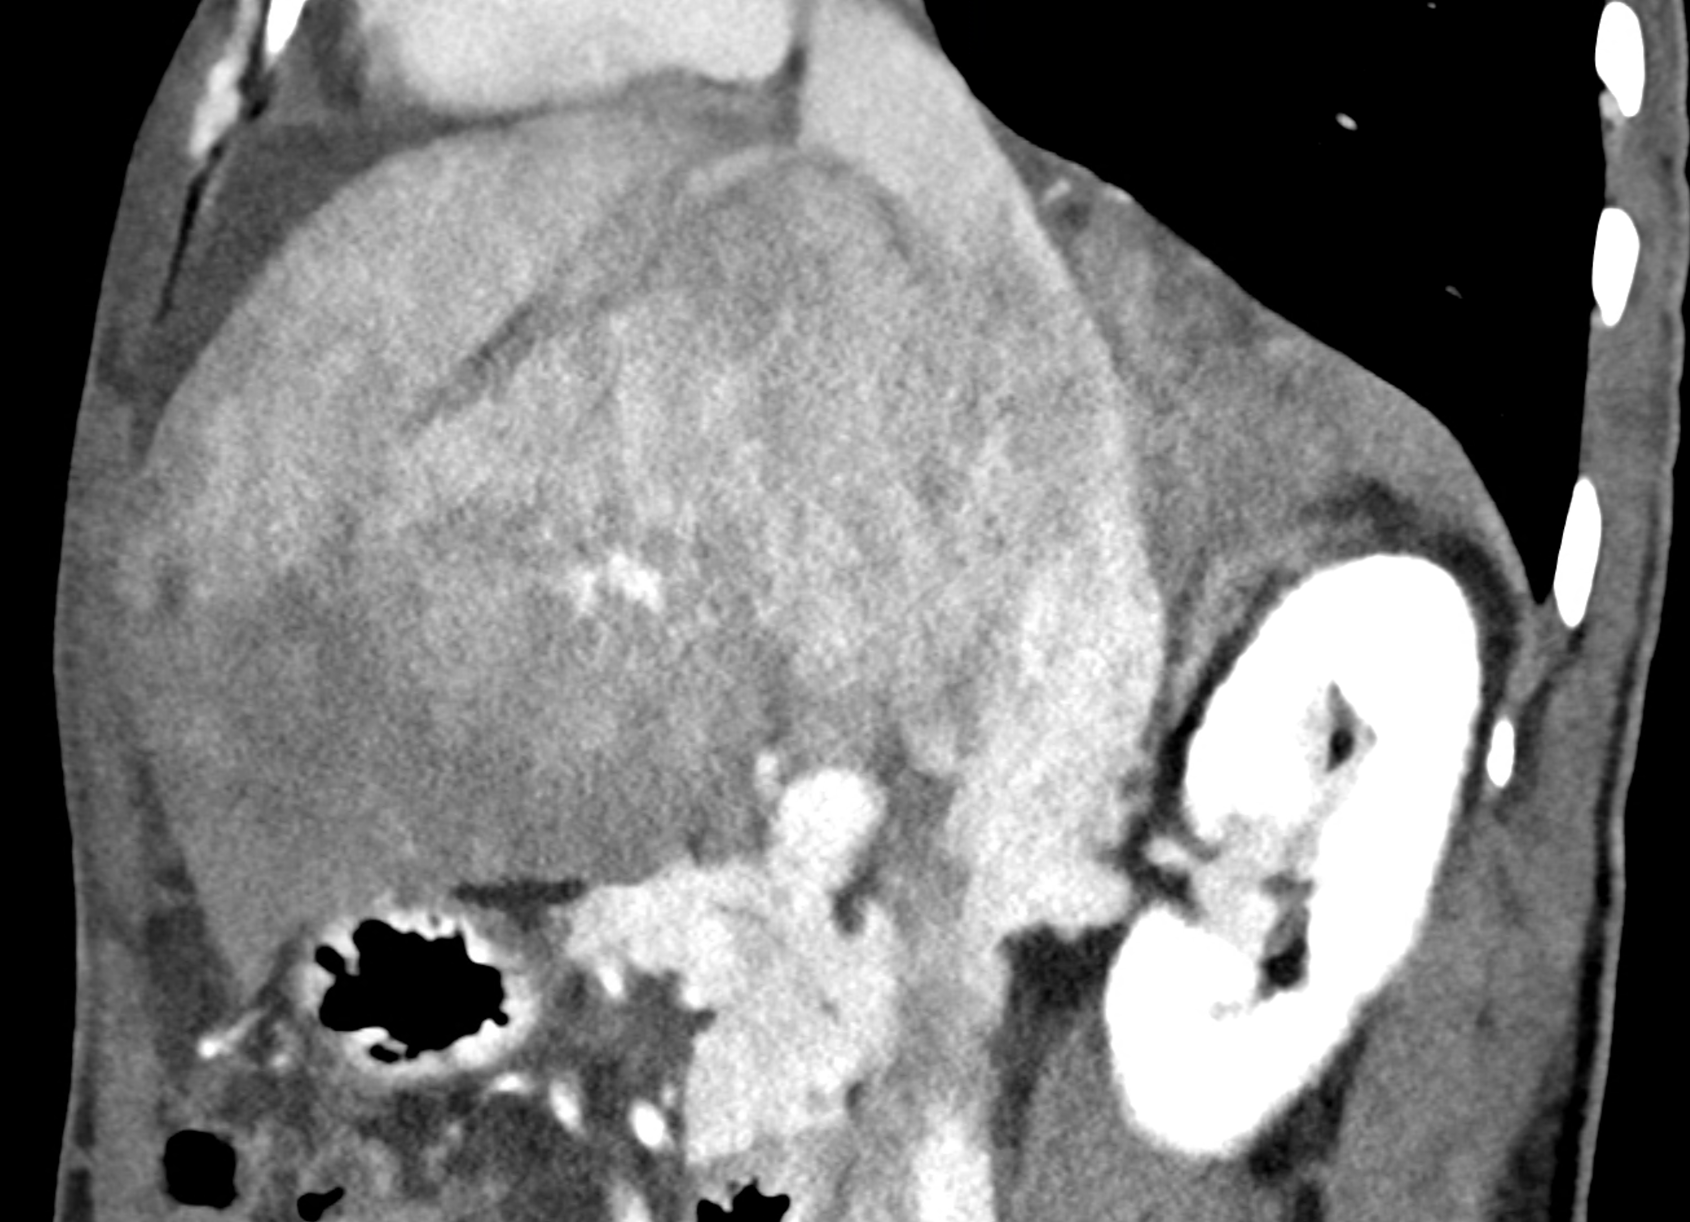

In CT images, BCS manifests as non-homogeneous enhancement of liver tissue in the arterial and especially in the portal phase, although in the portal phase may be increased, especially in the caudate lobe and left lobe, which are often hypertrophic (the hypertrophy and the enhancement is caused due to the possibility of the venous drainage directly into the inferior vena cava through the direct caudate veins), in contrast to the reduction in the right lobe. The portal vein is free, whereas even in the late phase, the hepatic veins and their contrast filling are not visible. Thrombotic occluded veins are hypodense.

A patient in his sixties with a Leiden mutation of factor V and a heterozygous prothrombin mutation presents with abdominal pain. Ultrasound examination reveals ascites and enlargement of the liver.There is enlargement of the liver, particularly the left lobe and caudate lobe. The hepatic veins are centrally filled with contrast medium due to reflux at the confluence with the inferior vena cava, and their radicular parts are thrombosed. There is typical chronic liver remodelling and the formation of centrifugal collateral circulation, including esophageal varices, and ascites is present in the abdominal cavity.

multiplanar reconstructions showing occluded radices of hepatic veins